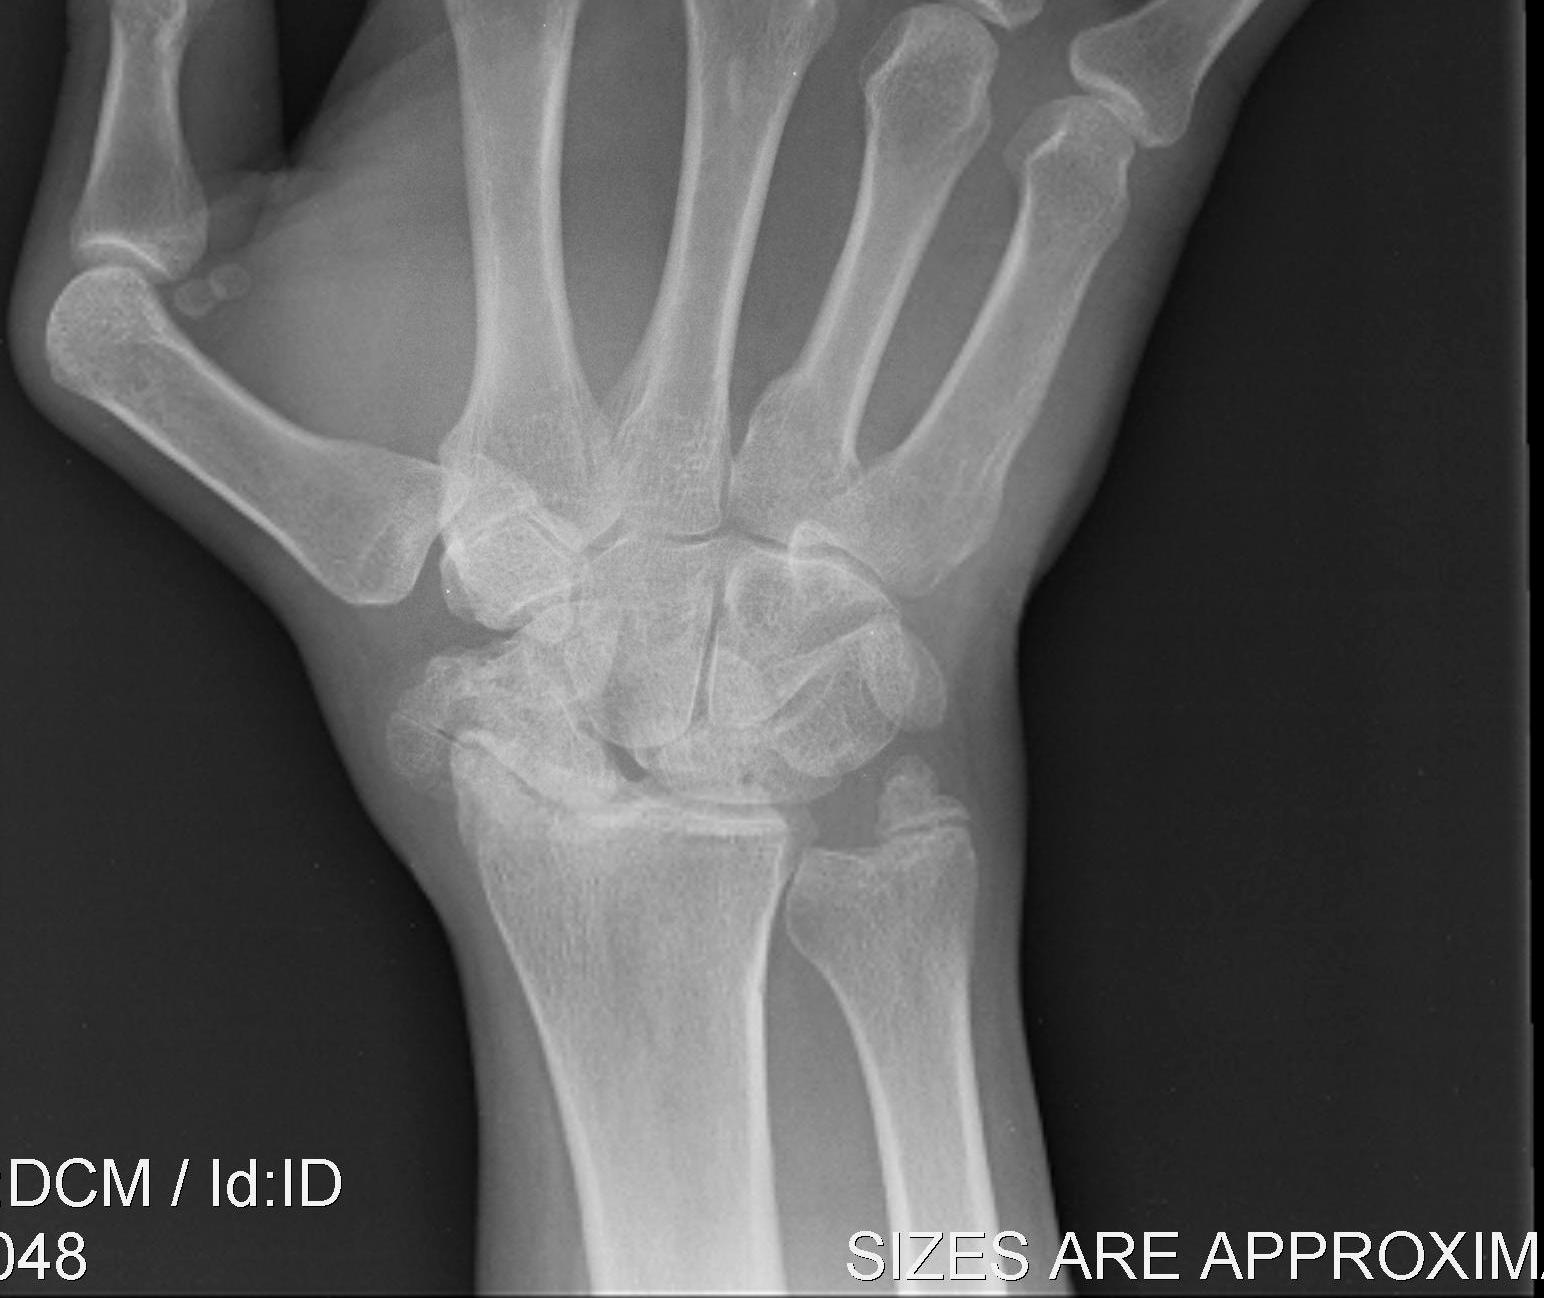

Definition

Scaphoid non union advanced collapse

Diagnosis

Xray / CT

- non union of scaphoid

- radio-scaphoid OA